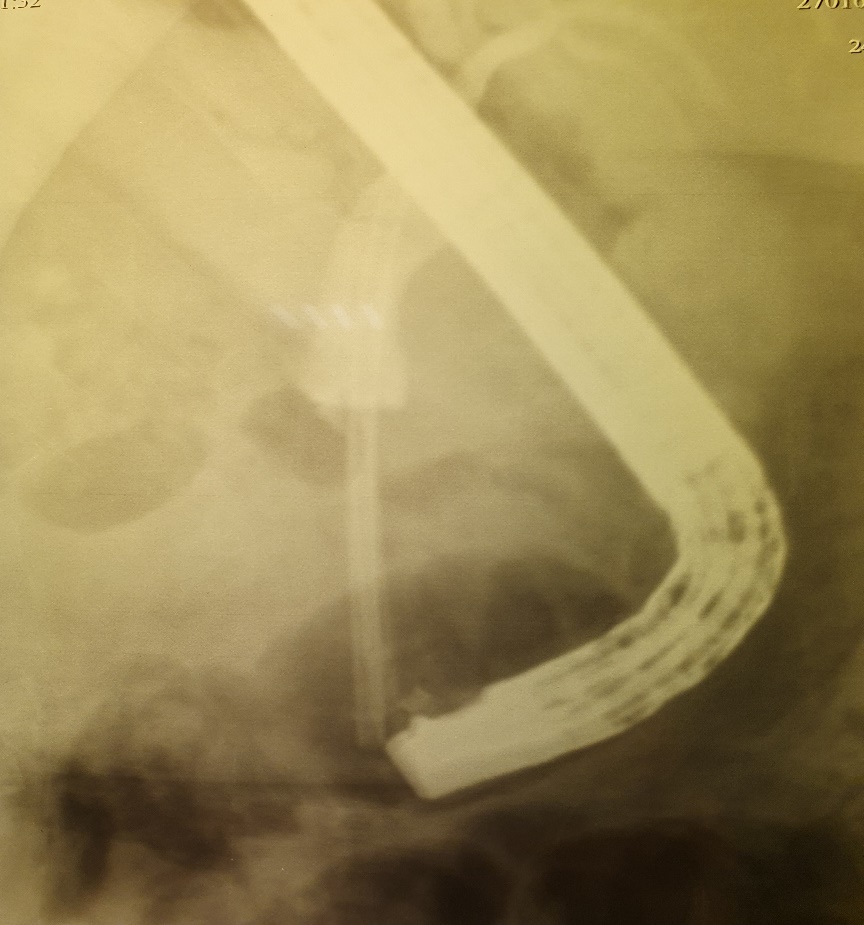

Состояние пациентов перед извлечением дренажа было удовлетворительным, боли в брюшной полости прошли или значительно уменьшились. Полость кист по результатам УЗИ и КТ полностью спалась или уменьшилась до щелевидной, что служило основным критерием целесообразности удаления внутреннего дренажа [4; 9]. В одном случае (2,77 %) киста, несмотря на нормальное положение стента, не спалась через три месяца. При МРТ-ХГ диагностировали протяженное сужение терминального отдела холедоха увеличенной головкой ПЖ. Проведена эндоскопическая ретроградная папиллотомия и установка стента Фанели в гепатикохоледох (рис. 4), после чего киста уменьшилась в размерах в два раза.

Рис. 4. Протяженный стеноз терминального отдела холедоха на фоне панкреатита. Эндоскопическая ретроградная папиллотомия и установка стента Фанели в гепатикохоледох